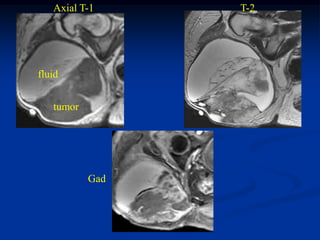

Case #270.2 Axial T-1 T-2 Gad 56 year male with painless soft mass in anterior thigh for 2 years

Axial T-1 T-2 fluid tumor Gad

• 263.

Sag T-2 Surgical specimen